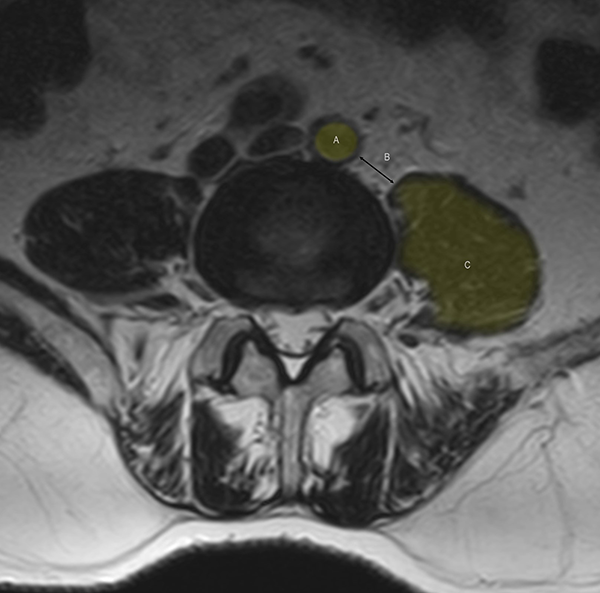

La factibilidad técnica de realizar el OLIF debe ser analizada en las imágenes preoperatorias. En el lado izquierdo de la columna lumbar, el corredor quirúrgico está limitado hacia medial por el borde de la aorta o la arteria iliaca izquierda y hacia lateral por el borde anterior del psoas (corredor o hiato OLIF). Si la distancia entre estas estructuras es menor a 1 cm, el riesgo vascular y la retracción necesaria sobre el psoas aumentan significativamente, por lo que se sugiere optar por una técnica diferente de fusión5 (Figura 2). Esta determinación puede realizarse mediante la medición en los cortes axiales del espacio discal en resonancia magnética (RMN) o tomografía computada (TC) sea en posición convencional o colocando al paciente en posición quirúrgica cuando se realiza el estudio.6 La vena iliolumbar o la vena ilíaca izquierda pueden ser identificadas en el fondo del corredor en el espacio discal L4-5. Cuando esto sucede, sugerimos evitar este abordaje, ya que la movilización de las mismas suele ser riesgosa y dificultosa. Una situación similar se da en los casos de anatomía transicional de la región lumbosacra, donde se modifica la división de los grandes vasos y habitualmente la localización de la vena iliolumbar.

Figura 2: Reconocimiento en imágenes (RMN) del espacio de trabajo en la técnica OLIF a niel L4-L5. A: Arteria Ilíaca izquierda, B: corredor OLIF. C: músculo psoas. Se sugiere un espacio entre A y C mayor a 1 cm.